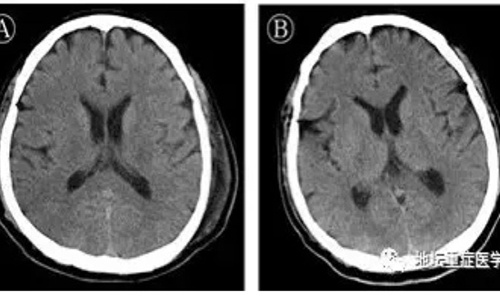

Ảnh chụp não bộ bị virus corona tấn công của bệnh nhân tại Khoa ICU, Bệnh viện Ditan Bắc Kinh. Ảnh: Ecns.

Bệnh nhân là nam giới, 56 tuổi, bị viêm não cùng lúc với viêm phổi. Phác đồ nghiên cứu não của bệnh nhân phát hiện virus corona xâm chiếm hệ thống thần kinh, giống như SARS và MERS đã từng gây ra.

Theo thông tin từ Ecns, bệnh nhân 56 tuổi đã hồi phục và được xuất viện vào ngày 25/2 vừa qua. Người này nhập viện một tháng trước vì suy hô hấp. Các bác sĩ đã giải trình tự gene trên dịch não tủy của bệnh nhân khi nhận thấy các rối loạn thần kinh, co giật sau nhiều ngày điều trị.